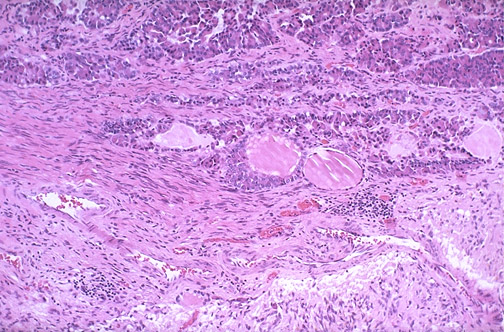

| At medium magnification of the pituitary gland, between the adenohypophysis and the neurohypophysis is the pars intermedia containing small cystic structures filled with a proteinaceous colloid-like material. Occasionally, Rathke's pouch remnants from embryogenesis of the pituitary can be seen in the pars intermedia. |